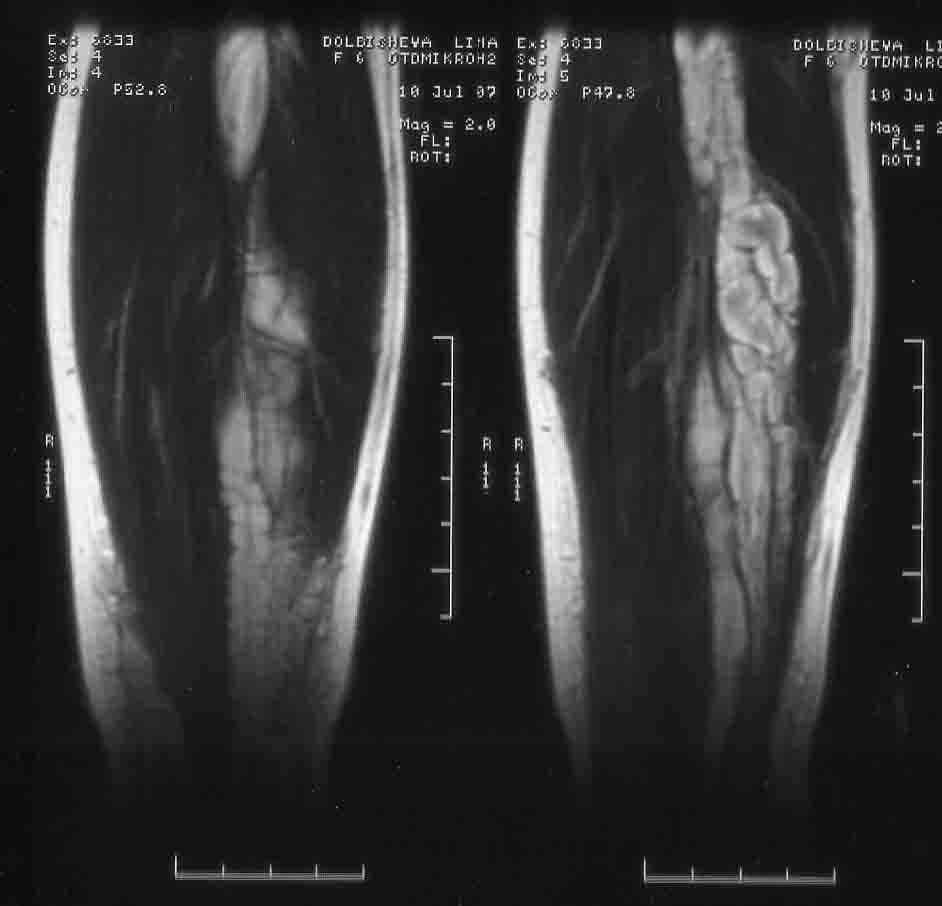

Обратились по поводу удлинения голени и деформации голенностопного сустава . В процессе обследования на МРТ выявлен нейрофтброматоз. Локализация процесса протяженная -от с\3 бедра до г\стопного сустава. Сонографически узлы распологаются как внутриствольно так и рядом.Если в стране специализированные центры и какая тактика была выбрана бы вами. Заранее благодарен за помощь.

Неврологических нарушений нет. Клинически -удлинение костей голени на 2 см и утолщение их , г\стопный сустав увеличен в размерах и несколько деформирован за счет наличия нейрофибром в мягких тканях. Диагноз подтвержден гистологически (удаление фибром в обл г\ст сустава) . Девочка активна и очень интелектуально развита.